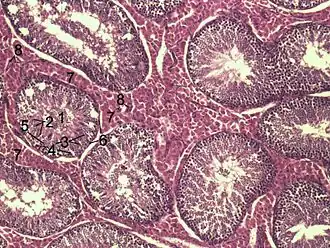

Histological section through testicular parenchyma of a boar. 1 Lumen of tubulus seminiferus contortus, 2 spermatids, 3 spermatocytes, 4 spermatogonia, 5 Sertoli cell, 6 Myofibroblasts, 7 Leydig cells, 8 capillaries